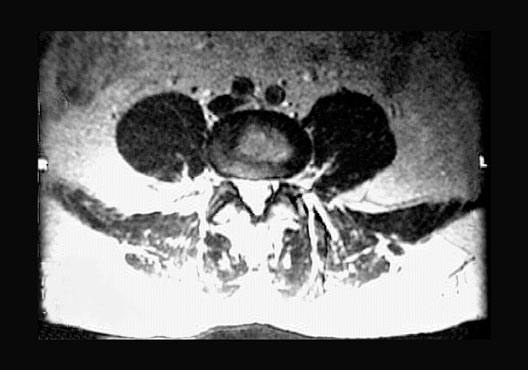

Lumbar Cross Section Zoom

Roll mouse over image to display labels.

1. Psoas major muscle

2. Nucleus pulposus

3. Anulus fibrosus

4. Intervertebral foramen

5. Contrast material in spinal canal

6. Facet joint